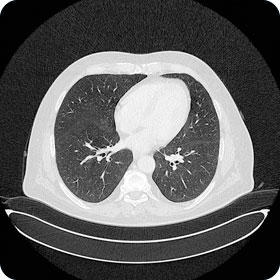

Thorax

| Sonographie | Notfall: Pneumothorax, Erguss |

| Konventionelles Röntgen | Infiltrat, Pneumothorax, kardiale Kompensation, Erguss, Rippenfraktur |

| CT | Lungenparenchymveränderungen, Staging, Lungenembolie, Aortendissektion, Raumforderung |

| MRI | Aortitis, Thoraxwandprozesse inkl. Entzündungen |